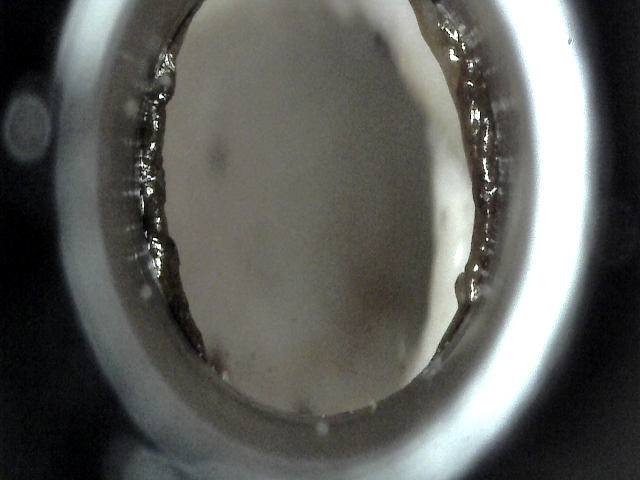

| 대상묘신청당시상태 | 뚱이는 밥을 챙겨준지 10년이 넘은 아이입니다. 그동안 화단,놀이터 등 이곳 저곳을 거쳐 몇년 전부터는 아파트 지하에서 밥을 주고 있었습니다. 나이가 10살이 넘으니 침을 많이 흘리고 밥 먹을때 입도 털고 하는 구내염 증상을 보여서 약을 먹이고 좀 나아졌다가 다시 증상이 보이면 약을 먹이고 하는 중이었습니다. 그러다가 몇달 전 옆구리에 뭐에 찔린건지 물린건지 심한 상처가 있었습니다. 피부에 구멍이 뚫렸고 피가 고여있고 그 부위가 염증때문인지 퉁퉁 부어올라 있었습니다. 중성화는 되어있지만 수컷이라 영역 싸움으로 인해 그동안 계속 상처들이 많아 왔는데, 이번엔 크게 다친 것 같아서 지원신청을 했는데 포획을 실패했습니다. 실패 후 할 수 없이 병원에서 약을 받아와서 약을 먹이고 환부에 약도 발라주고 하면서 그 상처가 조금씩 아물어 가고 있는 중인데 계속해서 다른 여기저기에 상처를 입고 구내염도 점점 심해지는 듯해서 다시 구조 결심을 하게됐습니다. 이번에는 이웃 캣맘께 도움을 요청드려서 함께 구조를 해서 무사히 성공했고 입원 시키게 되었습니다. |

| 치료전 대상묘 사진 |    |

| 대상묘 병명 | 구내염,충치,치아골절,고혈압,초기심근비대 |

| 치료과정 | 뚱이를 구조해서 병원에 데리고 갔습니다. 혈액검사 상으로는 다행이 별 이상이 없었습니다. 입은 구내염과 충치 , 아래 송곳니 골절이 있어서 발치를 하기로 했습니다. 그런데 심장 초음파 상으로 초기 심근비대로 나와서 계속 주기적 체크해야 한다고 했습니다. 그리고 평소에 뚱이 한 쪽 눈이 색깔이나 동자크기가 많이 달라서 걱정을 해왔었는데 선생님이 보시고 다른 안암 진단 받은 여러 아이들 사진과 비교해보신 후 뚱이도 안암이 의심이 될 수 있지만, 눈이라서 조직 검사가 너무 위험하고 어려운 상황이라서 추후 관찰을 요한다고 했습니다. 그리고 문제는 뚱이가 혈압이 180 으로 너무 높아서 당장 마취나 수술에 들어갈 수 없었습니다. 혈압이 높은 원인이, 포획되고 낯설고 무서운 곳에와서 스트레스로 인한 일시적인 것인지 지병으로 인한 것인지를 알기 위해서 일단 뚱이를 입원시키고 며칠 동안 혈압을 체크 해보기로 하셨습니다. 그 뒤 3일동안 계속 체크했지만 여전히 180 정도로 높게 나와서 고혈압 진단을 내리고 혈압약을 처방해서 먹이셨습니다. 혈압약을 2-3일 정도 먹이고 혈압이 120-30 정도로 안정된 것을 확인하신 후에 발치 수술에 들어갔습니다. 송곳니를 제외 한 전체 발치를 하였고, 골절된 아래 송곳니 뿌리를 제거하고자 했지만 뿌리가 턱뼈와 너무 가깝게 자리해있어서 자칫하다간 턱뼈가 골절될 위험이 있어서 송곳니 뿌리를 제거하지 않고 그냥 두었다고 하셨습니다. 수술 후 입원 상태에서 회복하고 살펴보기로 했습니다. 그런데 뚱이 심장 상태가 좋지 않아서 무리가 갈까봐 수액도 맞지 못하고 혈관주사와 복용약으로 진통과 아픔을 견뎌낼때 많이 안쓰럽고 걱정되었는데 다행이 잘 견뎌주고 하루하루 호전되는 모습에 안심을 했습니다 . 수술 잘 회복하고 혈압약 , 구내염약 처방 받아서 퇴원했습니다 . 2주간 약 먹이고 이번 주 월요일에 진료 받으러 병원 갔습니다. 뚱이 입 상태 보시고 구내염은 더이상 약 먹이지 않아도 되겠다고 하셔서 이제 구내염 치료 완료하여 후기를 씁니다. 혈압은 체크해보니 120 으로 유지되고 있어서 기존 혈압약 용량 그대로 더 처방 받아왔습니다. |